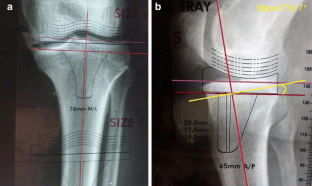

Fig. 2